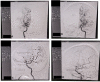

A 47-year-old woman with history of seizure disorder (semiology of seizure unknown), not well controlled with antiepileptic drugs since last 30 years presented with 1-year history of intermittent throbbing headache. On the day prior to admission, she experienced worst headache, followed by loss of consciousness. On regaining consciousness, she had neck pain without any focal neurological deficit, but examination was marked by positive meningeal signs. She had history of oral ulceration, photosensitivity and small joints pain for which no medical consultancy was sought until. Following relevant investigations, this case came out to be moyamoya angiopathy secondary to underlying systemic lupus erythematosus. She was put on immunosuppressive and immunomodulator as per recommendations. Among neurological symptoms, headache improved dramatically without any further seizure recurrence till the 6 months of follow-up.